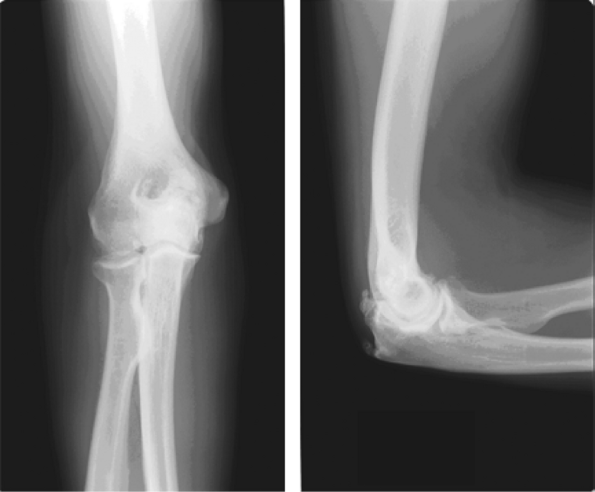

Figure 60-1

A lateral view of the right elbow, showing advanced osteoarthritis specifically involving the radiocapitellar joint. Notice the formation of osteophytes anteriorly and posteriorly. |

The characteristic radiographic features seen on the

anteroposterior and lateral radiographs of the elbow include

radiocapitellar narrowing, ossification, and osteophyte formation in

the olecranon fossa in almost all patients with osteoarthritis of the

elbow. Loose bodies and fluffy densities might be observed filling the

coronoid and olecranon fossae (Fig. 60-2).